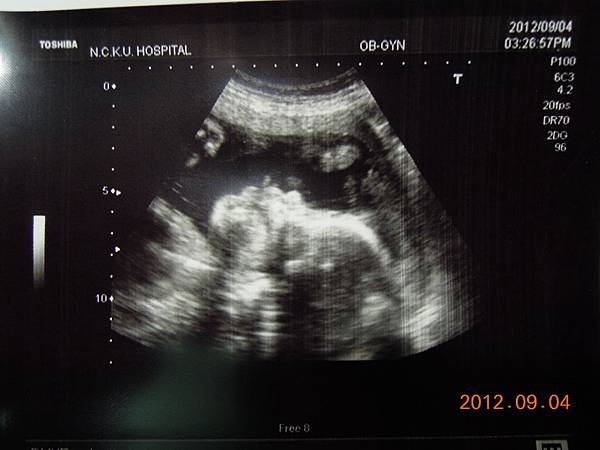

今天下午要做上次預約好的高層次超音波,一樣是到住院大樓四樓的超音波室等待~~

高層次超音波是用較精密儀器,並花較多時間仔細檢查胎兒的每一個部位和器官,所以還是把這兩千元花下去~

幫我檢查的應該是一位女醫師,這次檢查我媽也進去看,我記得上回檢查好像老公並沒有進去~不過上次是游醫師親自幫我做的檢查,今天因為游醫師剛好請假回來,掛號人數一定滿額,所以只好讓別的醫師服務囉~~

女醫師看起來超熟練,一邊照還會邊跟我解釋,這是逼逼的大腿,小腿,心臟,腎臟.....等等器官,一邊跟我媽聊天,說他生幾個....